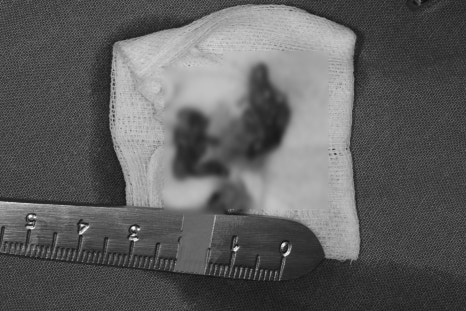

③ 병소 완전 제거 및 소파술 – 병소의 막을 포함해 골성 종양 조직 완전 제거

④ 골 재생 유도 및 봉합 – 병소 제거 후 필요 부위에 동종골 이식 + 콜라겐 멤브레인 적용

⑤ 병리검사 의뢰 (조직검사) – 제거된 병소는 병리전문의에게 이송되어 최종 진단

조직검사결과

✅ 진단 (Diagnosis)

Oral cavity, mandible, posterior, Rt., excision:

Consistent with periapical cyst, ruptured, with abscess formation.

→ 치근단 낭종(periapical cyst)으로 추정되며, 파열되어 농양(abscess)이 형성된 상태입니다.치아 뿌리 끝 부위에 생긴 낭종이 터지면서, 고름(농)이 발생한 것으로 확인됩니다.낭종이 커지거나 오랜 염증이 지속되면

파열과 감염이 동반될 수 있습니다.

📌 해석: 해당 병소는 염증성 치근단 낭종으로 판단되며,

이는 보통 치아 감염이나 외상에 의해 치아 뿌리 끝 부위에 생기는 대표적인 낭종입니다.